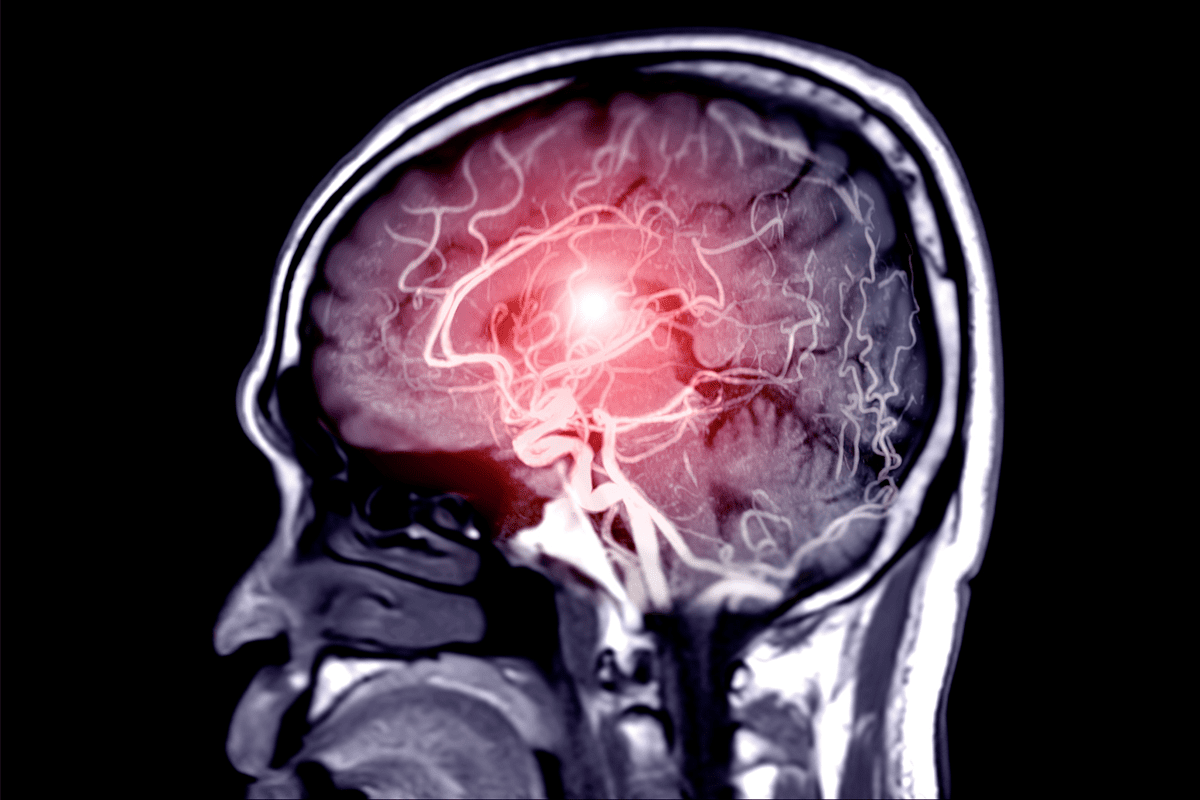

Oncology is a big area for regenerative cell therapy. But it’s not the only one. Now, research is looking at using regenerative cells for heart diseases, brain disorders, and bone problems, too.

This technology can help with many diseases, like Parkinson’s and Alzheimer’s. It can even fix damaged heart tissue. Our aim is to use it to make patients’ lives better.